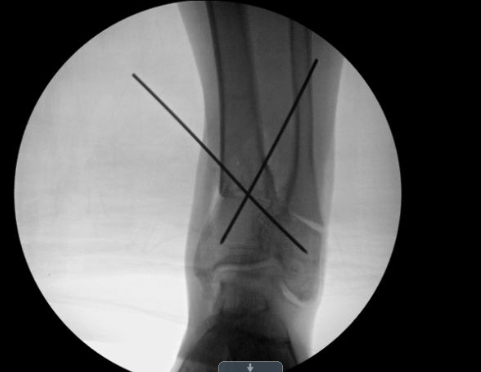

Ankle fracture repair

AF1